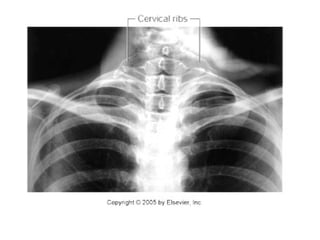

A cervical rib  ( i . e . , a rib arising from the anterior tubercle of the transverse process of the seventh cervical vertebra )  occurs in about 0.5% of humans. It may have a free anterior end, may be connected to the first rib by a fibrous band, or may articulate with the first rib .  The importance of a cervical rib is that it can cause pressure on the lower trunk of the brachial plexus in some patients, producing pain down the medial side of the forearm and hand and wasting of the small muscles of the hand .  It can also exert pressure on the overlying subclavian artery and interfere with the circulation of the upper limb see the figure in the previous slide . Cervical Rib

Thoracic outlet as seen from above. Note the presence of the cervical ribs  ( black )  on both sides. On the right side of the thorax, the rib is almost complete and articulates anteriorly with the first rib. On the left side of the thorax, the rib is rudimentary but is continued forward as a fibrous band that is attached to the first costal cartilage. Note that the cervical rib may exert pressure on the lower trunk of the brachial plexus and may kink the subclavian artery .

Thoracic outlet asseen from above. Note the presence of the cervical ribs ( black ) on both sides. On the right side of the thorax, the rib is almost complete and articulates anteriorly with the first rib. On the left side of the thorax, the rib is rudimentary but is continued forward as a fibrous band that is attached to the first costal cartilage. Note that the cervical rib may exert pressure on the lower trunk of the brachial plexus and may kink the subclavian artery .